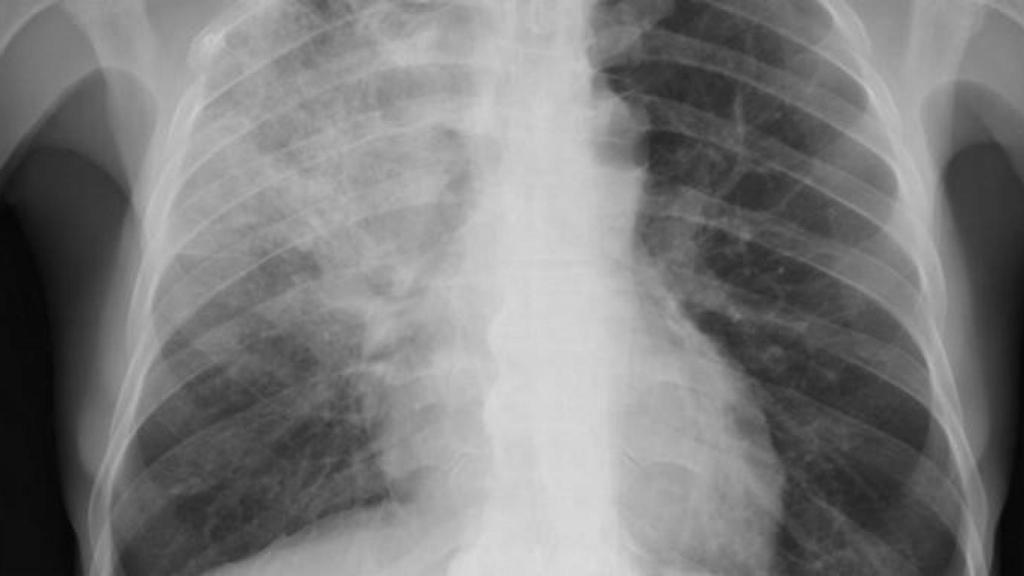

Radiografía de un paciente con neumonía / EUROPA PRESS